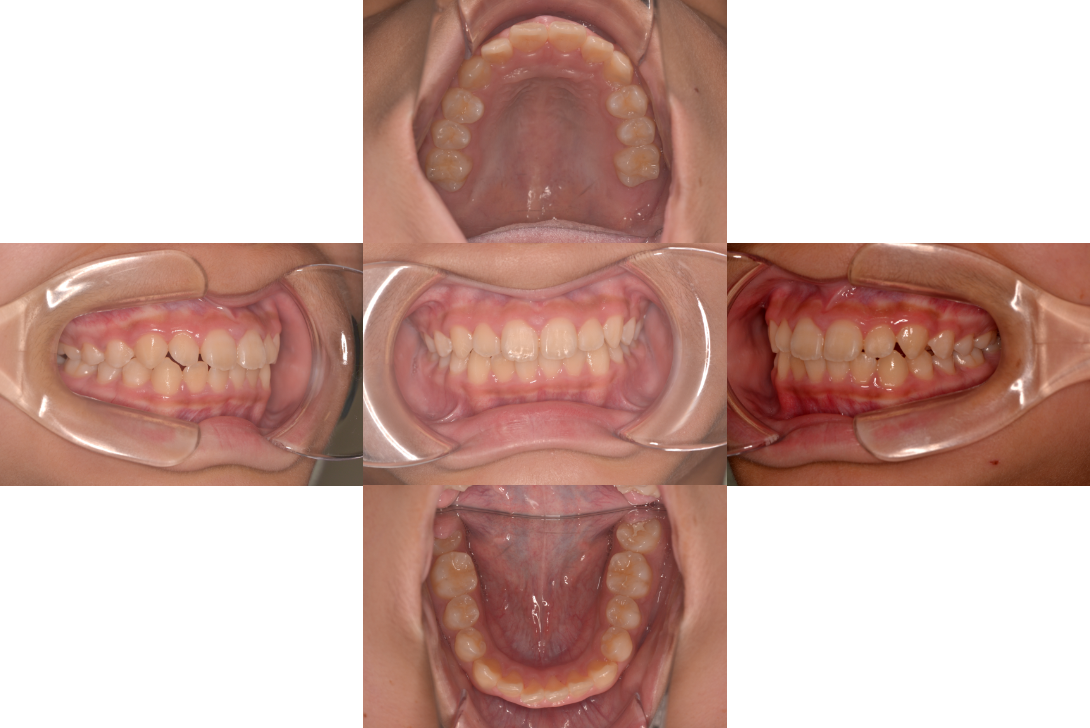

過蓋咬合を床矯正装置、下顎骨の前下方成長の促進で改善した症例

患者情報

11歳男性

主訴

咬み合わせを直したい

行った治療内容

床矯正装置、下顎骨の前下方成長の促進

治療のリスク

使用時間が短いと効果でない

治療期間

動的治療期間1年6か月

※ クリックして拡大することができます。